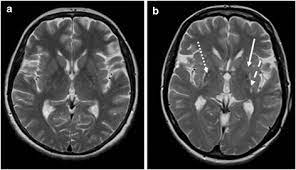

Humming Bird Sign Mickey Mouse Sign And Morning Glory Sign In Progressive Supranuclear Palsy Jalal Ma Menon Mk Menoufia Med J